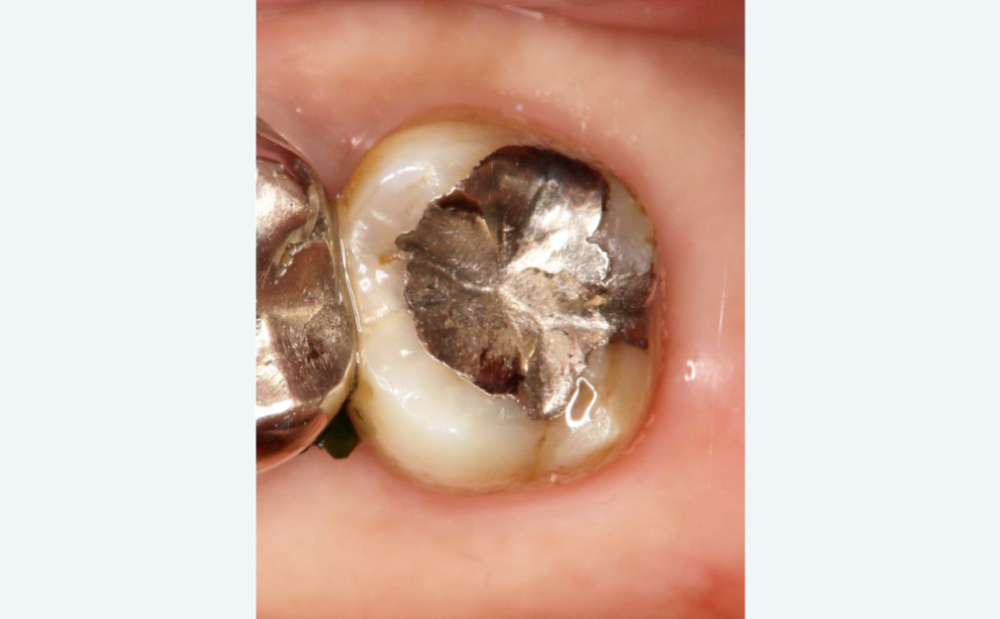

BEFORE

冷たいものがしみる

冷たいものがしみる

金属と歯の隙間から虫歯

金属と歯の隙間から虫歯

金属が気になる

金属が気になる

AFTER

むし歯を精密に除去

むし歯を精密に除去

セラミックインレーで修復

セラミックインレーで修復

見た目が自然で噛み合わせも改善

見た目が自然で噛み合わせも改善